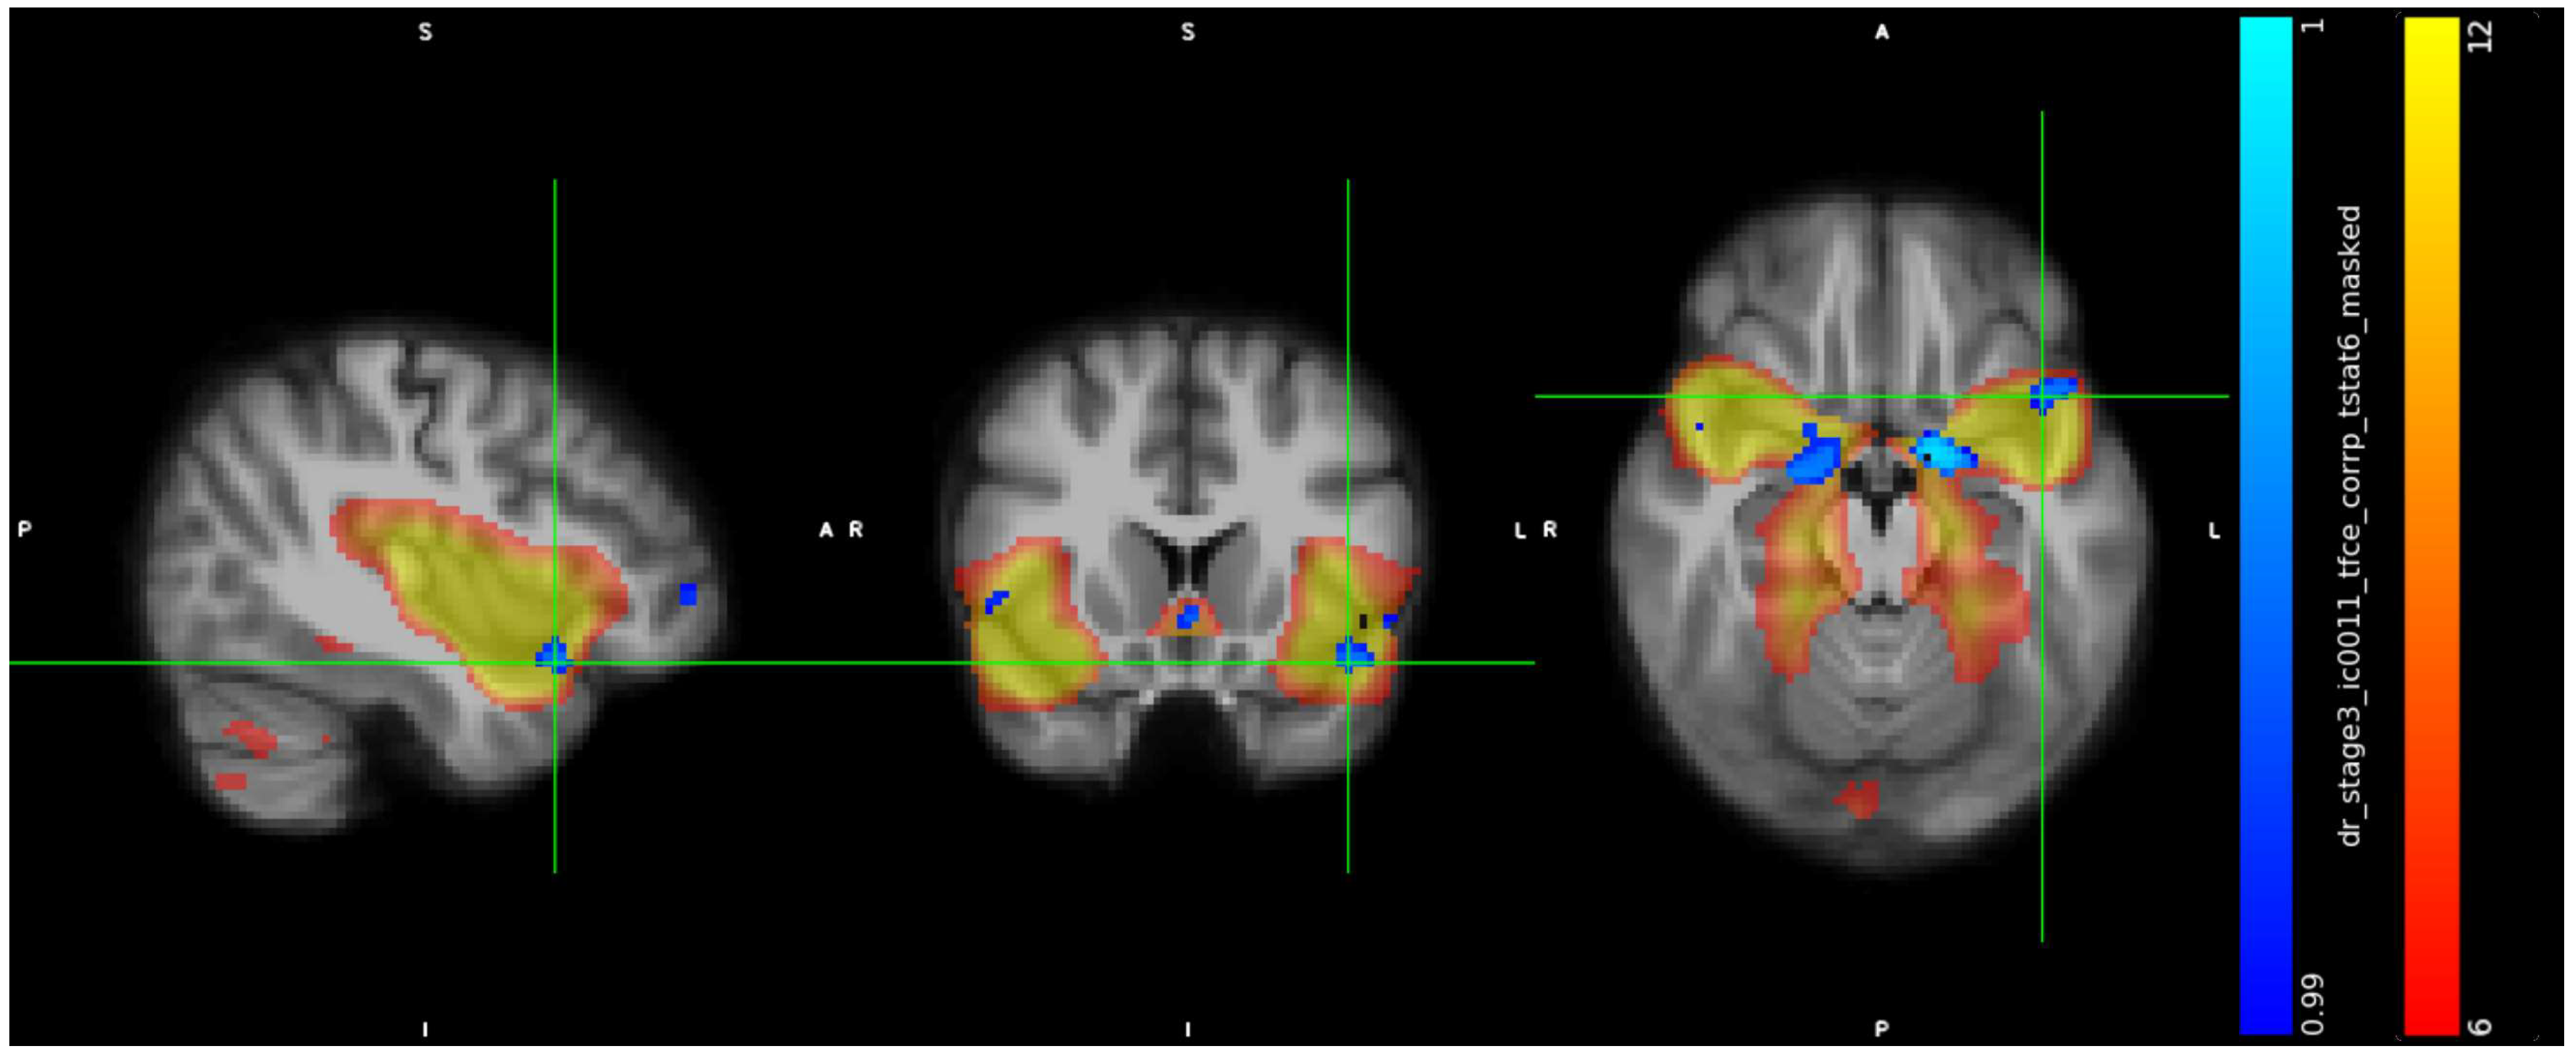

3.2. IC Analysis and Dual Regression